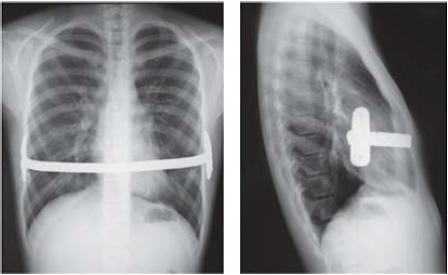

El procedimiento de Nuss: es una técnica muy poco invasiva. Se realiza una pequeña incisión para insertar una cámara y permitir al cirujano ver el interior del pecho. Entonces, a través de otras dos incisiones en cada lado del pecho, se inserta una barra de acero curvada debajo del esternón con la misión de invertir la depresión. No es visible desde el exterior y se mantiene durante dos a tres años para, finalmente, ser removido.

El procedimiento Ravitch: se realiza mediante una incisión en la zona media del pecho para retirar el cartílago. Después se colocan puntales de acero inoxidable para apoyar el esternón y se conectan las costillas correspondientes. Esto permite que el esternón sea levantado. Posteriormente, acabaran siendo eliminados en otra operación.